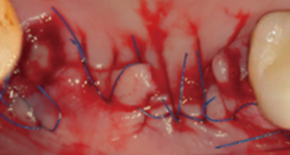

4. Bone grafting

5. SuturePain and swelling can be minimized and quick return to daily life is possible.